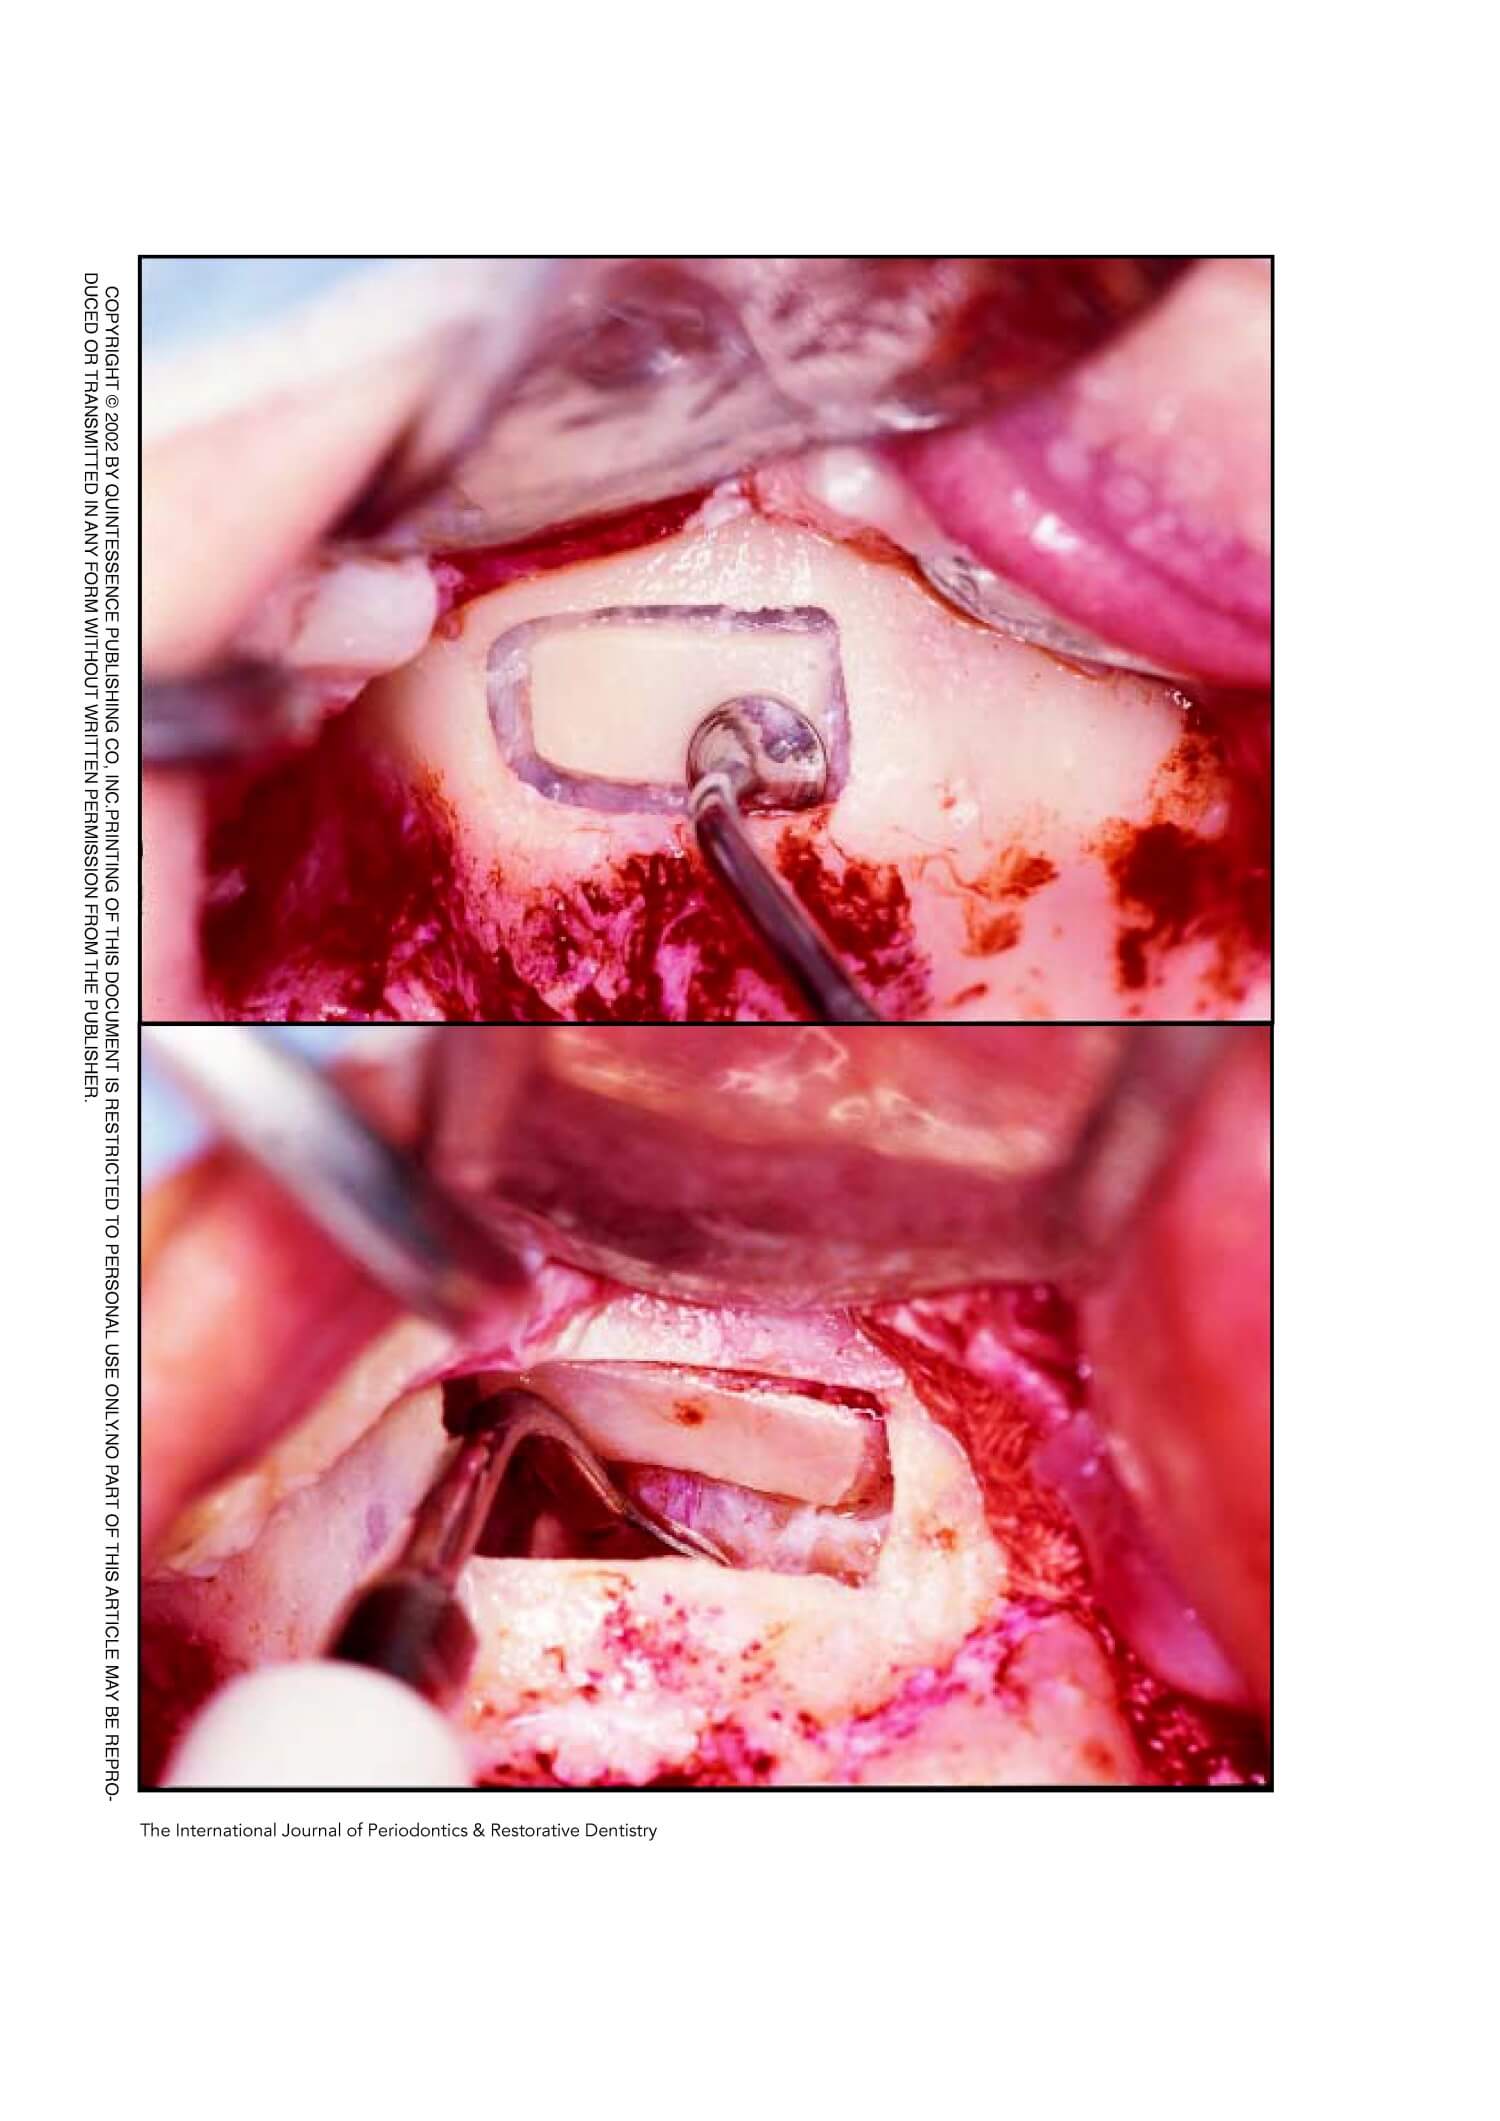

The Piezoelectric Bony Window Osteotomy and Sinus Membrane Elevation: Introduction of a New Technique for Simplification of the Sinus Augmentation Procedure

The Piezoelectric Bony Window Osteotomy and Sinus Membrane Elevation: Introduction of a New

Technique for Simplification of the SinusAugmentation Procedure